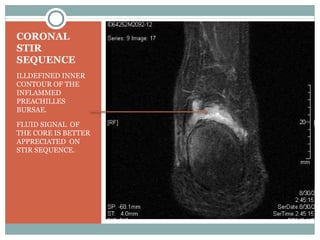

CORONAL

STIR

SEQUENCE

ILLDEFINED INNER

CONTOUR OF THE

INFLAMMED

PREACHILLES

BURSAE.

FLUID SIGNAL OF

THE CORE IS BETTER

APPRECIATED ON

STIR SEQUENCE.